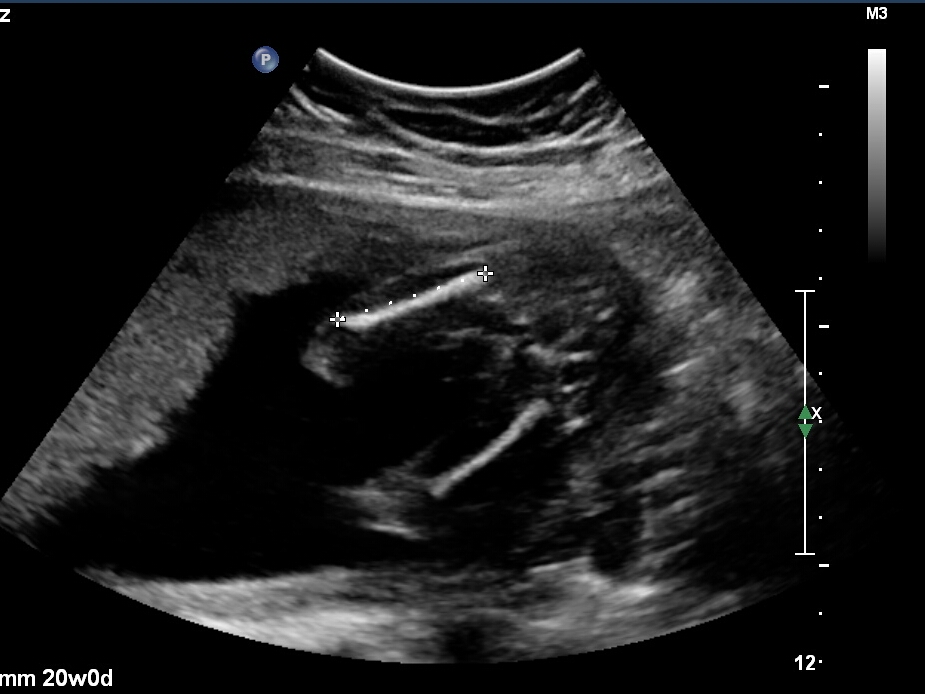

Just wondering if any gender clues can be seen in these pics? Attachment 37755Attachment 37756Attachment 37757